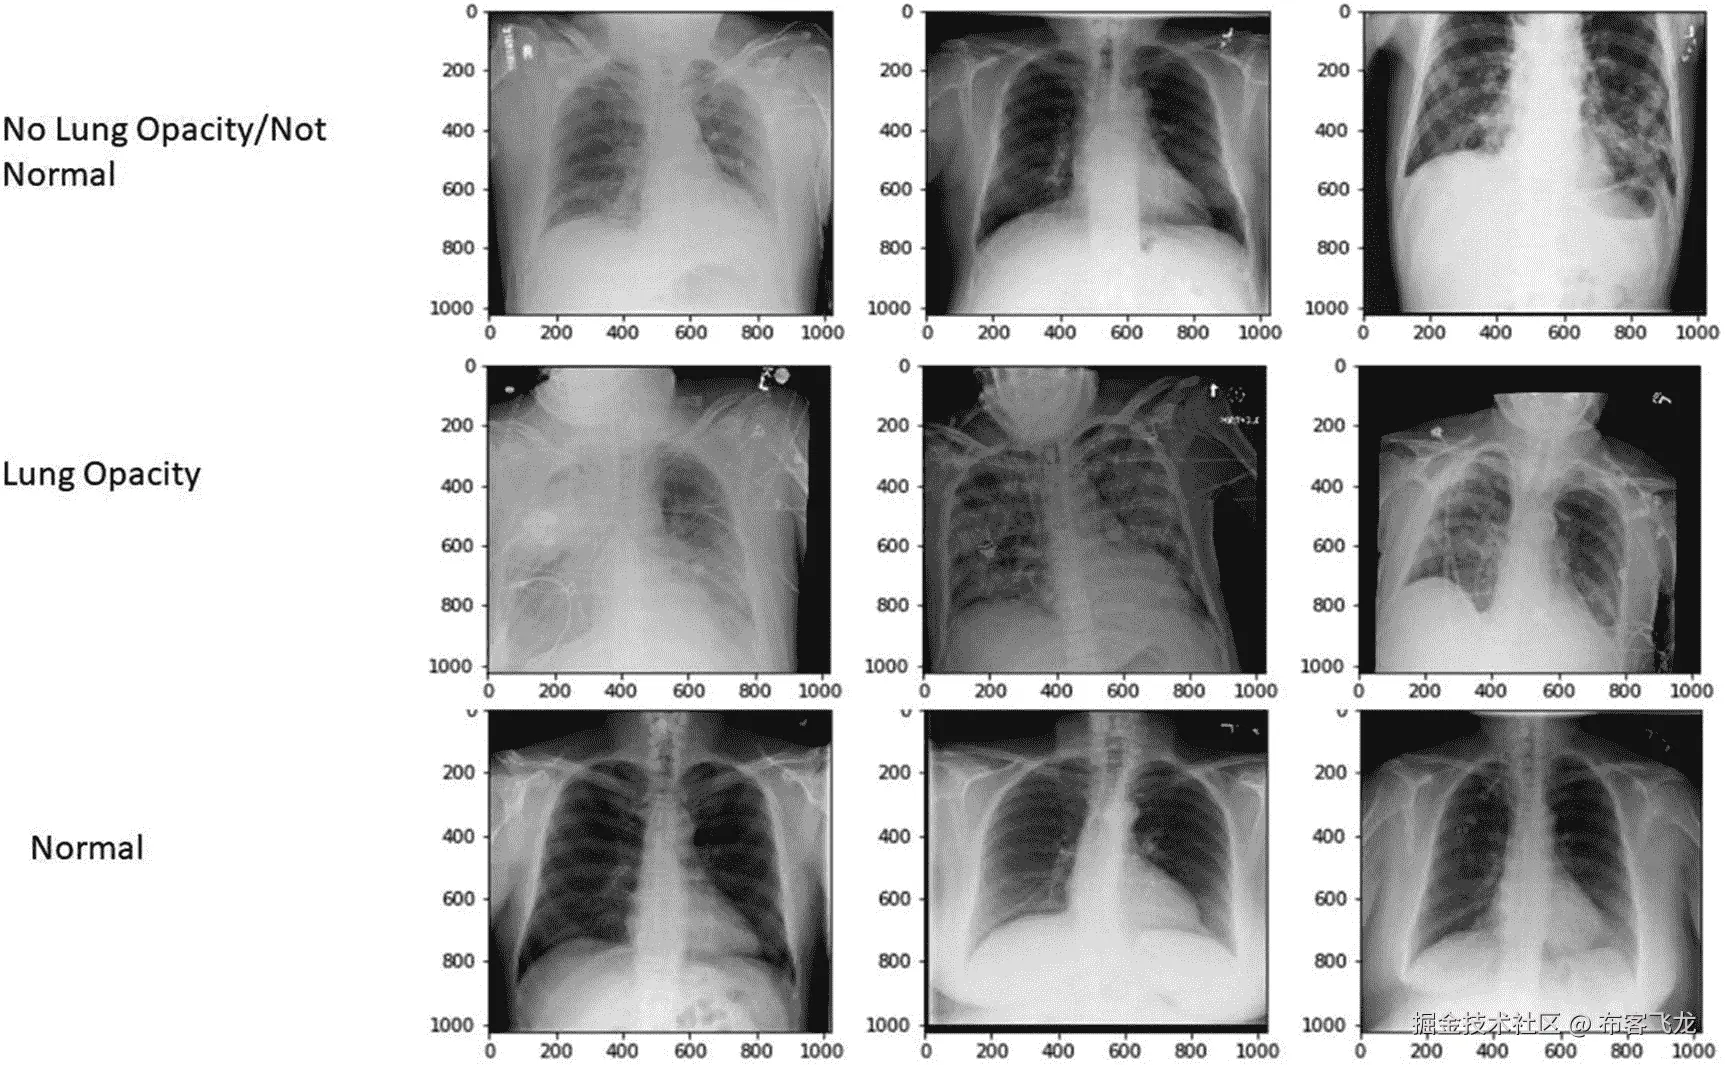

处理二维图像

你将接受北美放射学会的 RSNA 肺炎检测挑战。它组织在 Kaggle 上,拥有 DICOM 格式的数据。尽管该挑战旨在定位胸片上的肺活量,但 DICOM 元数据文件还包含以下图像标签:

• 标准

• 没有肺部阴影/不正常

• 肺部阴影

因此,您也将使用相同的标签进行影像分类。

接下来,非肺炎可以分为无肺部阴影/不正常和正常。正常的图像是健康胸部的图像。你不能说没有肺部阴影/不正常。让我们来看看其中的几个。

图 8-6 中的一些观察结果。

• 肺部阴影图像和无肺部阴影/不正常图像具有一些相似的特征。

• 电线和管子的存在,这表明除了目标值为 0 的肺炎之外,可能还有其他一些观察到的疾病。

• 在大多数情况下,间隙/不透明性(充满液体/病原体的间隙等)的性质。)对于两种类型是不同的,尽管由于类似于 COPD 或哮喘的外来物质在肺中的扩散,它可以重叠。

• 由于胸腔积液,液体或异物的积聚可以

• 渗出来让肺看起来更小。参见无肺部阴影/不正常行中的样本 3。

• 上述情况很容易与肺部阴影混淆,因此在这种情况下可能需要咨询几位放射科医生才能得出结论。

img/502837_1_En_8_Fig6_HTML.jpg

图 8-6

三种不同标签的样品